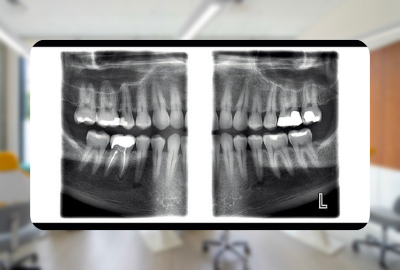

Panorex dental. This image is exceptionally useful in diagnosing a wide range of issues. The image is either displayed digitally on a computer or. Without this critical piece of data we can sometimes miss pathologic lesion such as tumors or cysts extra teeth and a whole host of other conditions that need surgical treatment in a timely fashion.

Now a standard part of the imaging protocols at many practices digital panoramic x-rays provide a large amount of diagnostic information and great efficiency. OPG otherwise known as panorex or orthopantomogram is a full mouth panoramic scan dental x-ray of the lower and upper jaws. Our Technology June 20 2018 by Reedley Dental 0.

Diagnostic images of a patients complete dentition are produced almost instantly with a digital panoramic imaging system and the newest systems provide. It is commonly performed by dentists and oral surgeons in everyday practice and. Tracy Robinson is a well-trained Veneta Dentist call us today. Dental Digital Panoramic X-ray. Without this critical piece of data we can sometimes miss pathologic lesion such as tumors or cysts extra teeth and a whole host of other conditions that need surgical treatment in a timely fashion. Initially the patient will sit in a chair with their chin on a small ledge. Now a standard part of the imaging protocols at many practices digital panoramic x-rays provide a large amount of diagnostic information and great efficiency. Your dental hygienist doesnt have to constantly come in and out of the room to change film saving you time. During the panorex X-ray the patient is asked to bite down on a special tool that assists the operator in positioning the patients head in the correct position.

A panorex is imaging machinery that is capable of providing a full view of the upper and lower jaws teeth temporomandibular joints and sinuses. Dimensions of Dental Hygiene is a monthly peer-reviewed journal that reconnects practicing dental hygienists with the nations leading educators and researchers. Access Dental providing professional dental care. It is commonly performed by dentists and oral surgeons in everyday practice and. Here you can discover how panoramic radiography works. This image is exceptionally useful in diagnosing a wide range of issues. Welcome to the new age of dental x-ray technology.